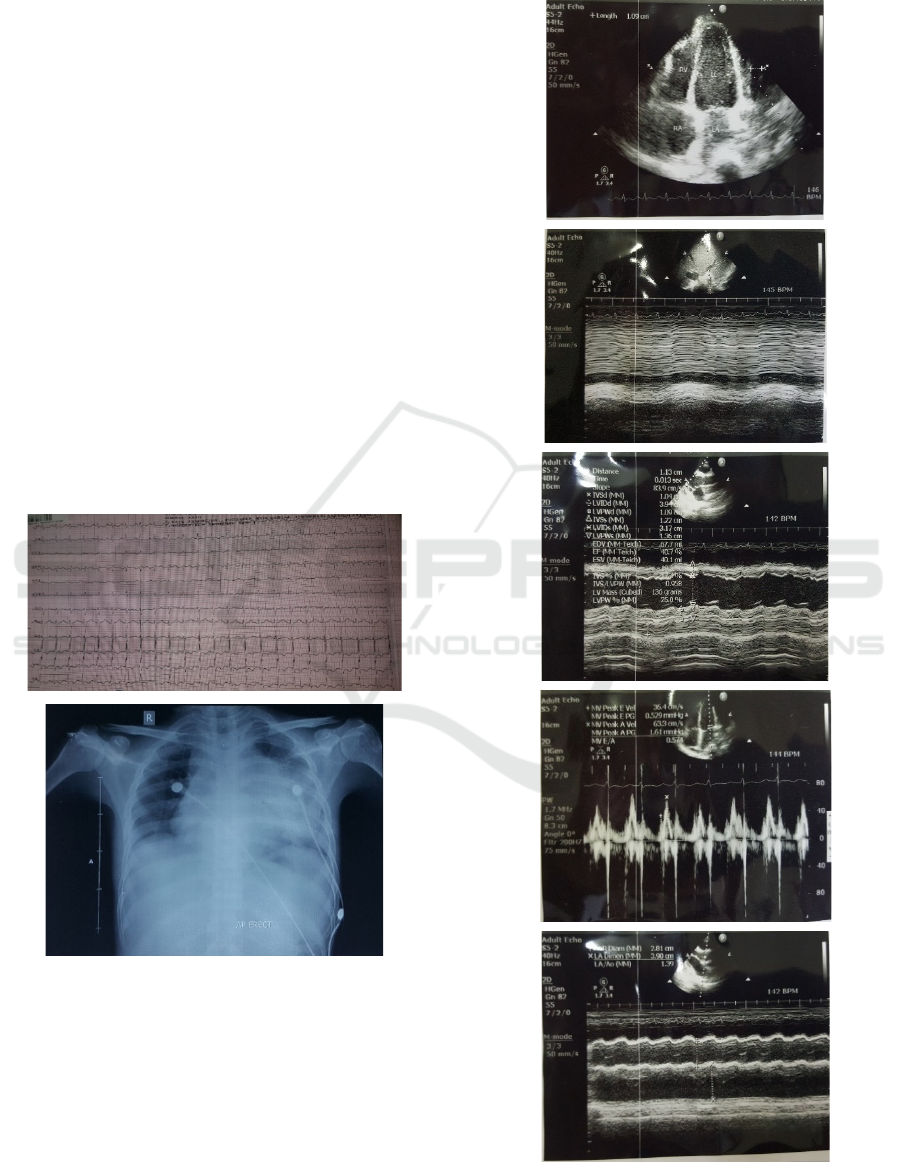

mg/dL. The patient had done electrocardiographic

(ECG) and Chest X-Ray examination (Figure 1), the

conclusions from echocardiography examination and

Doppler Tissue Imaging were pericardiac effusion

and constrictive pericarditis (Figure 2 and Figure 3).

Figure 1: The ECG and Chest X-Ray of the Patient. The

impressions of (ECG) examination were sinus tachycardia

and LVH. Cardiomegaly and infiltrates were found on

Chest X-Ray examination.

Figure 2: The Echocardiography Results of the Patient.

Figure 3: Doppler Tissue Imaging of the Patient. The e'

medial velocity was 25 cm/s and the e’ lateral velocity was

lower (9 cm/s). There was an increase in the difference of

mitral flow rate during inspiration and expiration > 25%.

There was also an increase in backflow of diastolic hapatic

veins at expiration.

Heart spaces

and

large blood vessels in the normal

position. Heart valves are good. There is no defect in the

heart chambers. There is a thickening of the pericardium

parietal and visceral with adhesion of the pericardium in

some places. There is a light pericardium effuse. The

systolic and diastolic function of LV decreases.